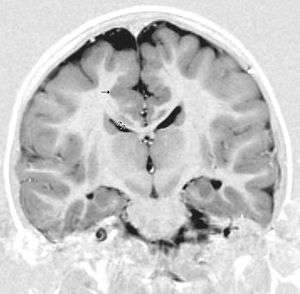

There are different tests or methods used to determine GPR56 expression or visuals of the brain to analyze the specific sections that are affected. These tests for example, using animals such as mice, RNAi, Behavioral assay, Electron microscopy, CT scan, or MRI demonstrate different results that concludes an affected BFPP patient.[13] MRI's reveal either irregularity to the cortical surface suggestive of multiple small folds or an irregular, scalloped appearance of the gray matter-white matter junction.

Neuroimaging The diagnosis of polymicrogyria is typically made by magnetic resonance imaging (MRI) since computed tomography (CT) and other imaging methods generally do not have high enough resolution or adequate contrast to identify the small folds that define the condition. The cerebral cortex often appears abnormally thick as well because the multiple small gyri are fused, infolded, and superimposed in appearance.[11]

- Radiological findings (MRI) demonstrated symmetric generalized polymicrogyria with decreasing anterior-posterior gradient, most prominent in frontoparietal cortex.[11]